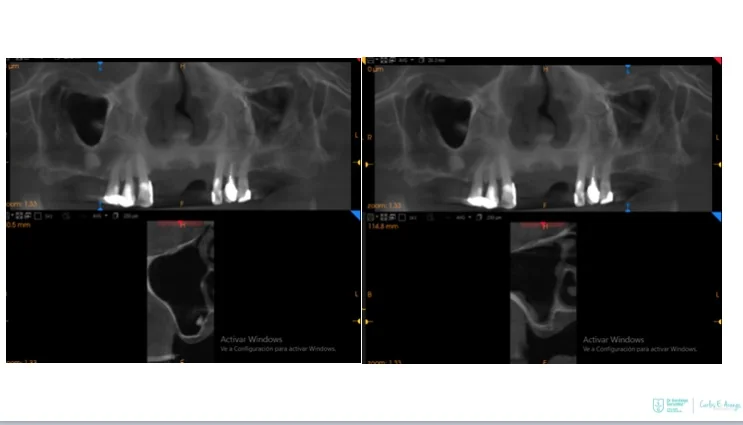

Two straight anterior implants and two implants tilted up to 45º in the posterior - Immediate Function (fixed provisional bridge)

For patients meeting criteria for immediate loading of implants - Graftless Procedure: Bone grafting is avoided by tilting the posterior implants, utilizing available bone.